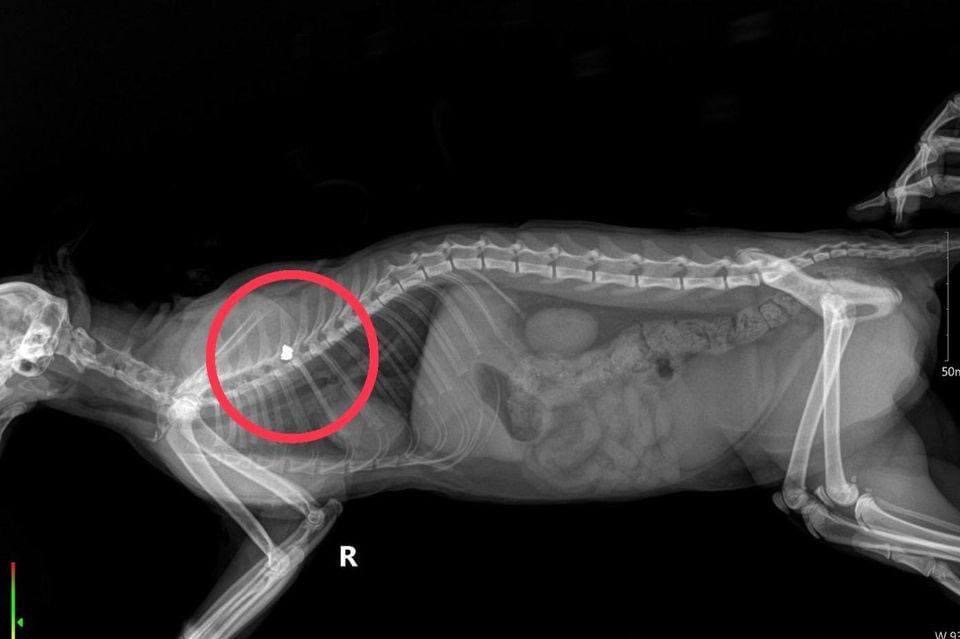

News จิตใจทำด้วยอะไร! สาวสุดช็อกแมวนอนนิ่ง เจอรอยกระสุนทั่วตัว วอนผู้รู้ช่วยอธิบาย คนร้ายใช้อาวุธอะไรทำร้ายน้อง?? Published 2 ปี ago on มีนาคม 25, 2024 By Admin_Tojo Share Tweet สาวเจอแมวที่เลี้ยงไว้นอนนิ่ง โกนขนมาเจอรอบกระสุนเพียบ ขอผู้รู้ตอบคำถาม น้องโดนอาวุธอะไร ผู้สื่อข่าวโตโจ้นิวส์รายงานว่า กรณีเพจ Drama-addict โดยนพ.วิทวัส ศิริประชัย โพสต์ข้อความผ่านเฟซบุ๊ก ระบุว่า ลูกเพจฝากมา รบกวนสอบถามสัตวแพทย์หน่อยครับจ่าคะ สวัสดีค่ะ จ่าพอทราบไหมคะ ข้อมูล anatomy ของแมวพอดีแมวที่เลี้ยงไว้บ้านสวนถูกยิงค่ะแมวถูกยิง กระสุนฝังใกล้กระดูกสันหลัง ตำแหน่งซี่โครง 4 แมวจะมีผลอะไรกับเค้าไหมคะ จะพิการไหมคะ จะได้วางแผนชีวิตตัวเองได้ค่ะ (อาการตอนพบ นอนนิ่งจนมดตอม วางให้ยืน ไม่ยืน ขาหลังไม่มีแรง แต่หมอเอาเข็มจิ้มๆยังกระตุกหนีได้ค่ะ)ตอนไปพบ นอนนิ่ง หมดคันไฟตอมตัวเต็ม แต่ตายังใสค่ะตอนนั้นยังไม่รู้ว่าโดนยิงค่ะนี้ตอนพาไปหาหมอ เพราะแมวไม่สบาย เดินไม่ได้ มีแผล นึกว่าไปโดนแมวที่ไหนกัดค่ะ พอพาไปหาหมอ โกนขน ชัดเจนค่ะ ถ้าอยากให้จ่าช่วยโพส เพื่อสอบถามผู้รู้ได้ไหมคะ เพราะพยามโพสในกลุ่มปืน กลุ่มแมว ไม่มีใครตอบได้เลยค่ะ1.กระสุนแถวกระดูกสันหลัง ซี่โครงที่ 4 น้องจะพิการไหมคะ หรือมีเอฟเฟคต์อะไรไหมคะ2.อาวุธที่ทำน้องร้ายคืออะไรคะ ขนาดกระสุนเท่าไหร่3.จากบาดแผล ยิงใกล้ หรือยิงไกลคะ โพสต์ดังกล่าวได้รับความสนใจอย่างมาก เพราะภาพที่เห็นล้วนทรมานใจจากการกระทำที่โหดร้าย นอกจากนี้ยังมีคนเข้ามาตอบคำถามของลูกเพจจ่าว่า ลูกที่ฝ่าออกมา ลูกเบอร์ 1 ของปืนอัดลมเป็นปืนที่ ชาวบ้านทั่วไป ยังมีแอบซื้อขายทั่วไป ปกติเอาไว้ยิงนกหนูที่มารบกวนผลผลิต แต่ถ้าลูกหลานเฮงซวยเอาไปยิงเล่นมันก็ยิงแมวยิงหมาไปเรื่อย ลองเดินๆสำรวจพวกก๊วนเด้กๆที่ยิงนกตกปลาย่านนั้นเดี๋ยวก็เจอตัว จากสัตวแพทย์ที่เล่นปืน1.ข้อมูลไม่มากพอจะตอบได้แม่นยำ2.ลูกปืนอัดลมเบอร์ 13.ยิงจากไม่ไกลนัก ไม่เกิน 100 เมตร 1.ตอบไม่ได้ว่าจะส่งผลกระทบอะไรกับสัตว์ไหม ขึ้นอยู่กับว่ากระสุนฝังอยู่บริเวณไหน โดนสันหลังไหม ต้องถามหมอที่ผ่ากระสุนออกครับว่ากระสุนฝังในชั้นไหน ชั้นกล้ามเนื้อ ชั้นใต้ผิวหนัง หรือโดนกระดูกสันหลังด้วยแต่เท่าที่ดูจากฟิล์มคร่าวๆ (อยากดูฟิล์มทั้งด้าน vd / lateral แต่ในโพสมีแค่ lateral) ส่วนตัวผมคิดว่าน่าจะอยู่ในชั้นกล้ามเนื้อหรือชั้นใต้ผิวหนังครับ ซึ่งถ้าเป็นแบบนั้นอาจไม่ได้ส่งผลกระทบอะไรกับระบบประสาทครับ ทั้งนี้ทั้งนั้น ต้องได้รับการตรวจระบบประสาทเพิ่มเติมก่อนและดูการตอบสนองกับยาลดอักเสบไปก่อน 3-4 วัน จะสามารถบอกได้มากขึ้นครับ2.คิดว่าเป็นกระสุนปืนลมครับ ไม่ก็ .22 แต่คิดว่าเป็นปืนลมมากกว่า3.จากแผลบอกไม่ได้ว่ายิงใกล้หรือไกลครับ เพื่อไม่พลาดข่าวสารดีๆ อย่าลืมกดติดตามพวกเรา TOJO NEWS Share this:TwitterFacebookLineLike this:Like กำลังโหลด... Related Topics:#TOJONEWS #โตโจ้นิวส์Featured Up Next สามีจะเป็นลม! ความใจบุญของภรรยา ซื้อกบขาเจ็บมา 50 บาท แต่ล่าสุดจ่ายเงินไป 20,000 บาท Don't Miss ใกล้ความจริง! เงินดิจิทัล 10,000 บาท จุลพันธ์ แถลง! ไม่เกินสิ้นปีถึงมือประชาชนทุกคน Continue Reading Advertisement Advertisement Latest Trending Videos News15 นาที ago หมออ๋อง แฉยับ! รัฐบาลจะโกง ไม่มีทำโครงการตรงๆ ปีศาจอยู่ในรายละเอียด News20 นาที ago วีระยุทธ์ โพสต์เตือน! ค่าไฟส่อแพงขึ้น 5 บาท/หน่วย News3 ชั่วโมง ago ณัฐพงศ์ จี้ กทม. ปัญหาโรงขยะอ่อนนุช ผ่านมา 4 ปี เพิ่งขยับตอนเลือกตั้ง News13 ชั่วโมง ago จับกุมหญิง ลักลอบขนเต่าดาวฯ ออกนอกประเทศ!! News1 วัน ago อันตราย! ก้างปลาติดคอแต่ไม่เอาออก อาจทะลุออกคอ จุดเส้นเลือดใหญ่ News2 วัน ago หนังสือด่วนที่สุด! สั่งที่ว่าการอำเภอทั่วประเทศ 878 แห่ง เริ่ม 1 พ.ค.69นี้! ขายของถูกให้ปชช. CLIP5 เดือน ago ฟังข่าวดีก่อนสิ้นปี 2568 (random clip) CLIP5 เดือน ago เช็คพลังงาน ดึงดูดความรัก Horoscope2 ปี ago ดวงความรักที่จะเกิดขึ้นกับคุณ กับ อ.สาธกา พรหมญาณ